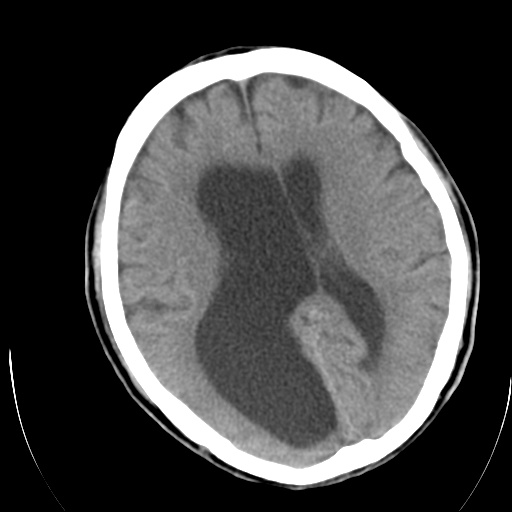

以下是引用泪洒红尘在2009-3-23 19:53:00的发言:[br]第四脑室以上脑室明显扩大,脑沟脑裂无明显增宽加深征象,符合交通性脑积水ct表现。

以下是引用xulianj在2009-3-23 20:31:00的发言:[br]右侧侧脑室扩大,中线结构左移,考虑梗阻性脑积水,建议mri检查。